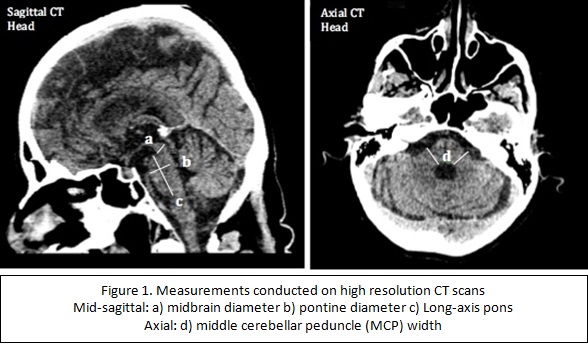

HOT ! 胸部CT・MRIマニュアル 1 Brain injury after cardiac arrest: pathophysiology

Brain injury after cardiac arrest: pathophysiology。胸部・胃部・マンモグラフィ・CT・MRI・エコー・眼底・心電図の読影。月経随伴性気胸疑いフォローアップ ( UTE のこんな使い方。